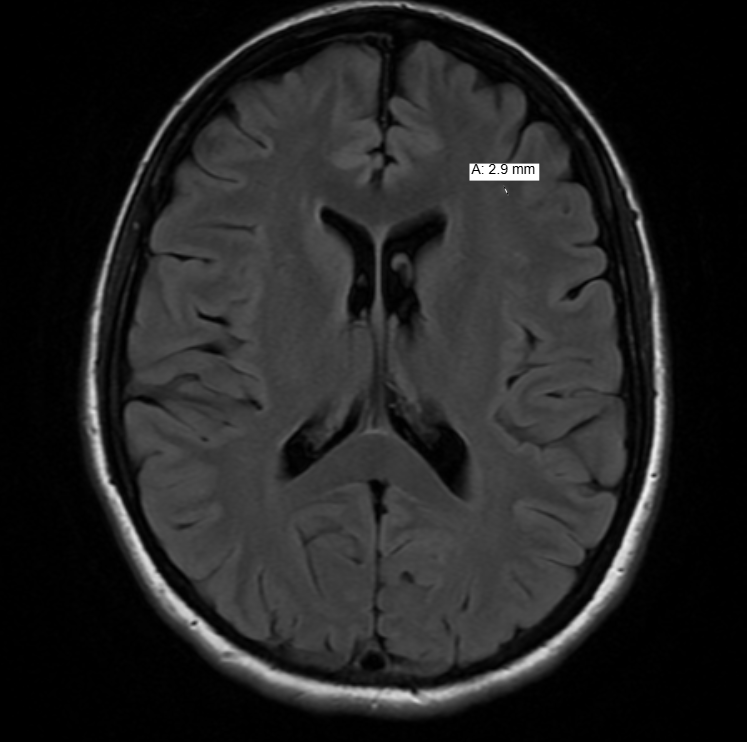

Since 2022, I’ve had a standing date with an MRI machine every year—my own personal Groundhog Day, except instead of a rodent predicting the weather, it’s a giant magnet peering into my brain and predicting, well, me. The scans always show the same old stroke souvenirs (thanks for the memories, 2022!), but otherwise, things have been reassuringly uneventful until last week.

A few hours later, the results dropped, and—cue the dramatic music—my hunch was right. White Matter Hyperintensity. Left frontal lobe. The start of Small Vessel Disease—a phrase that hovers ominously, hinting at the possibility of dementia down the road, like those balloon ladies at the back of a marathon, always just behind you, no matter how hard you push. But honestly, I wasn’t surprised. My body has been sending up distress flares for months, and I’ve been logging the symptoms like a runner logs miles: